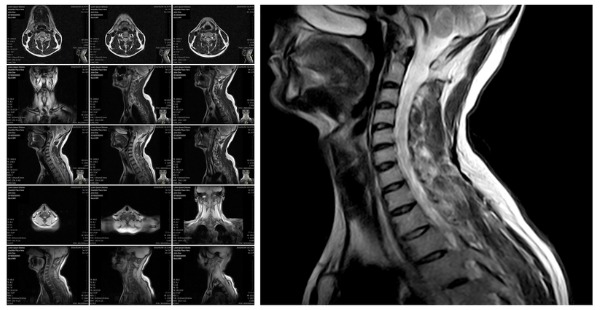

NDI Spinal MRI Interpretations And Reading Services

An MRI examination of the spine displays the anatomy of the vertebrae that compose the spine, ligaments that bind the vertebrae together, along with the disks, spinal cord and the openings between the vertebrae where nerves pass.

Patient symptoms that prompt physicians to recommend spinal MRIs include back pain coinciding with fever, signs of brain or spinal cancer, lower back injuries, chronic back pain, MS, bladder problems and weakness or numbness in legs and bladder problems. An MRI is a very sensitive imaging test of the spine commonly used in typical clinical practice.

Radiologists at NDI read and interpret spine, thoracic, cervical and lumbar (lower spine and back) MRIs to identify degenerative disc disease, herniated discs and spinal stenosis. A lumbar MRI specifically examines the lumbar section of the spine. This is the area where back problems typically originate.

Radiologists at NDI read MRIs to detect ruptured/herniated/bulging discs or to determine if a disc is being pressed against a nerve such as the sciatic nerve. Dr. Berns and his staff read MRIs to find tumors affecting the nerves or bones of the spine. Types of cancer that are commonly detected by teleradiologists at NDI in the spine spread there from the prostate, lungs or breasts.

Radiologists at NDI frequently detect compression fractures of the spine while reading MRIs. Docs at NDI look for joint inflammation, bony overgrowth, spinal cord tumors, abscesses, arthritis and bone loss when reading MRIs. Radiologists at NDI look for areas of the spine that have poor blood supply, an infection, nerve damage or congenital problems.